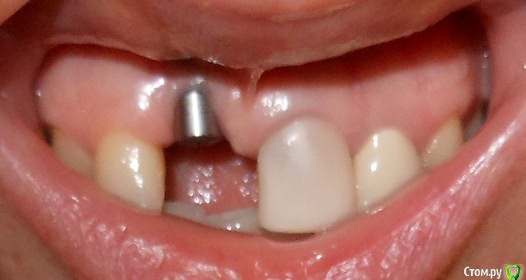

Ната-ли Опубликовано 16 сентября, 2015 Поделиться Опубликовано 16 сентября, 2015 Всем удачного дня!Совсем не знаю как мне быть ?! Просверлили нечаянно корень зуба, пришлось ставить имплант Astra Tech. Имплант стоит уже год. Болел пол года при эмоциональных , физических, психологических нагрузках ))) Имплан мой очень не любил спорт и горячий душ))) Но если просто лежать на диванчике, то имплант чувствовал себя прекрасно. Сумомед и кетанов стали моими неразлучными друзьями.) Кстати, нос тоже болел...наверное и нос как-то нечаянно задели имплантом))) Сейчас вроде по-легче.... Сделала снимок импланта в 3д. Когда расшифровали, я была в полном стрессе... Всё содержимое снимка, с моим вращающем черепом загрузить не получается...вот сделала скрин...(вид с боку)Имплант на 11-ом зубе , впереди держится только за слизистую, судя по снимку кости нет ...куда делась не знаю...то ли ушла куда-то, то ли так имплант вкрутили ...мимо кости???Выпиливать имплант не хочется....я же ещё часть кости потеряю ? Имплант беспокоит иногда (ноет, пульсирует), но я уже привыкла. Десна ушла вверх, может пластику десны сделать? (Хотя ни у кого из моих знакомых ни чего не получилось, слизистая, взятая с нёба , отваливалась вместе с нитками.Десна становилась ещё хуже и выше.)Не думаю, что "нарощенная" десна укрепит имплант ))),... но будет по-эстетичнее какое-то время...но потом десна вероятно снова поднимется, держаться-то ей не на чем )))Короче, что делать с десной не знаю...ПО поводу импланта ??? Думаю поставить пока коронку и посмотреть что будет дальше ? Я передними зубами есть ни чего не буду ))) просто для красоты хотя бы))) И буду ждать когда имплант сам выкрутиться ))) Или как ??? Ссылка на комментарий